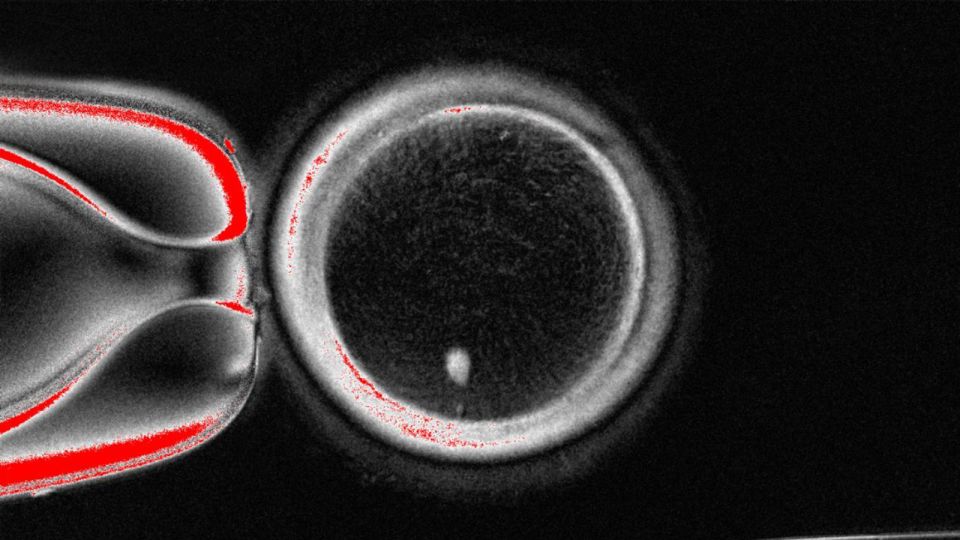

Scientists have developed a method to create functional human eggs from skin cells, which could potentially offer a new approach to infertility treatment. This proof-of-concept study was published in Nature Communications and involved transplanting the nucleus of a skin cell into a donor egg that had its own nucleus removed. The resulting eggs share DNA with the person who donated the skin cell and can be fertilised with another individual’s sperm. Although the technique is not yet ready for clinical use, it is considered a significant step in fertility research. However, all embryos resulting from this study were chromosomally abnormal, indicating that further research is needed to ensure safety and efficiency.